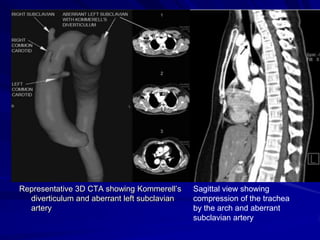

Representative 3D CTA showing Kommerell’s

diverticulum and aberrant left subclavian

artery

Sagittal view showing

compression of the trachea

by the arch and aberrant

subclavian artery